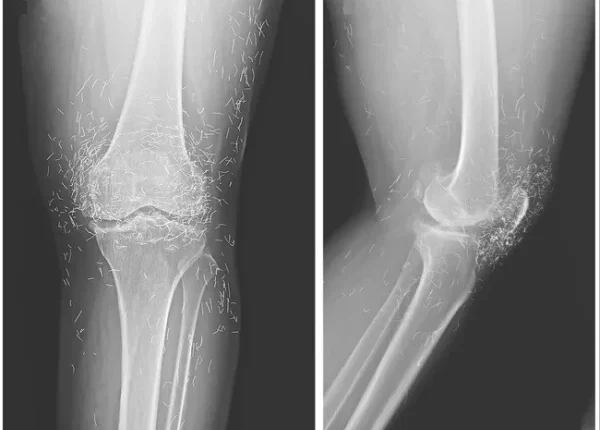

مذکورہ بالا تصویر ایک 65 سالہ خاتون کے گھُٹنے کے ایکسرے کی ہے جس میں دیکھا جا سکتا ہے کہ گھٹنے کے گرد سینکڑوں چھوٹے سونے کے تارموجود ہیں۔

بعد ازاں خواتین کے گھٹنے کا ایکس رے کیا گیا اور جو چیز سامنے آئی، وہ گھٹنے کے اندر سونے کے انتہائی باریک تار تھے۔ دراصل یہ تار اکیوپنکچر کے دوران باقاعدہ طریقے سے اندر چھوڑ دیے گئے تھے تاکہ جسمانی تحریکی اثر برقرار رہے۔